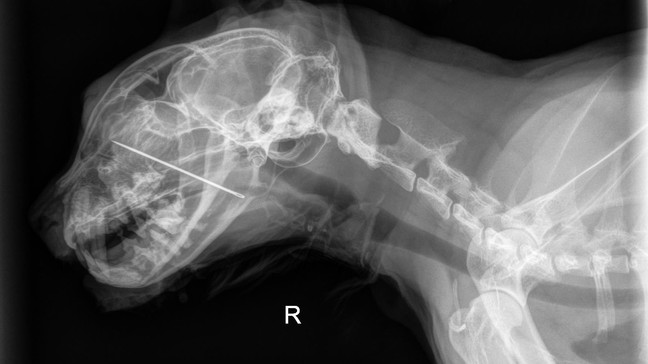

Portland vet saves Kevin, curious cat who ate sewing needle, impaled nasal cavity

PORTLAND, Ore. — A Portland cat named Kevin let his curiosity get the better of him when he ate a sewing needle, which then impaled into his nasal cavity - but luckily, a vet team was able to save the day!

Kevin decided to try a little taste of the sewing needle.... which became lodged in his mouth, impaling through his hard palate and into his nasal cavity.

At DoveLewis, it was decided that Kevin needed a sedated oral exam to find the cause of the problem. That’s when the team discovered the sewing needle embedded in Kevin’s mouth, with the blunt end pressing against the base of his tongue.